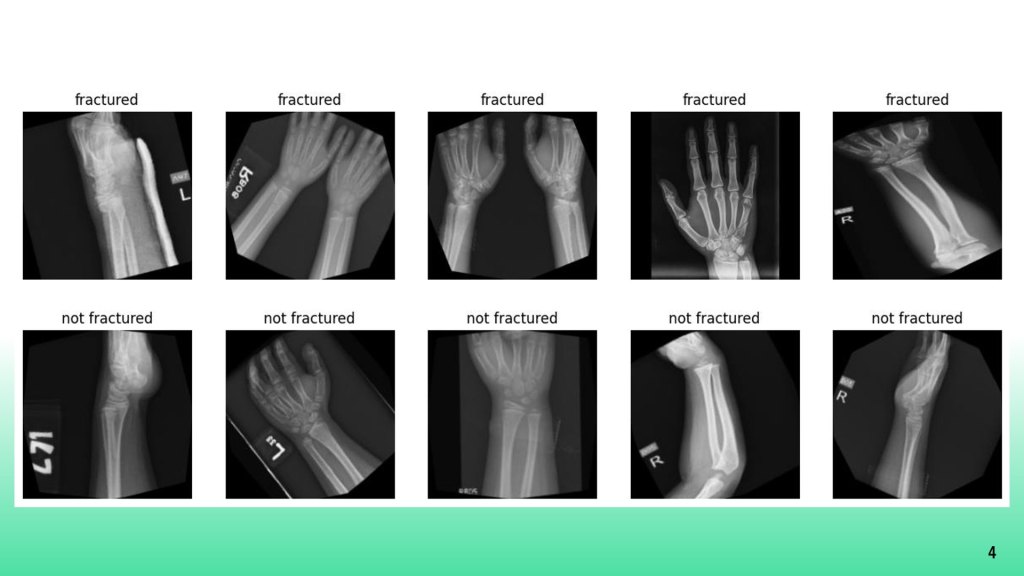

Bone Fracture Classifier

Convolutional Neural Network trained to classify bones as fractured (1) and not fractured (0)